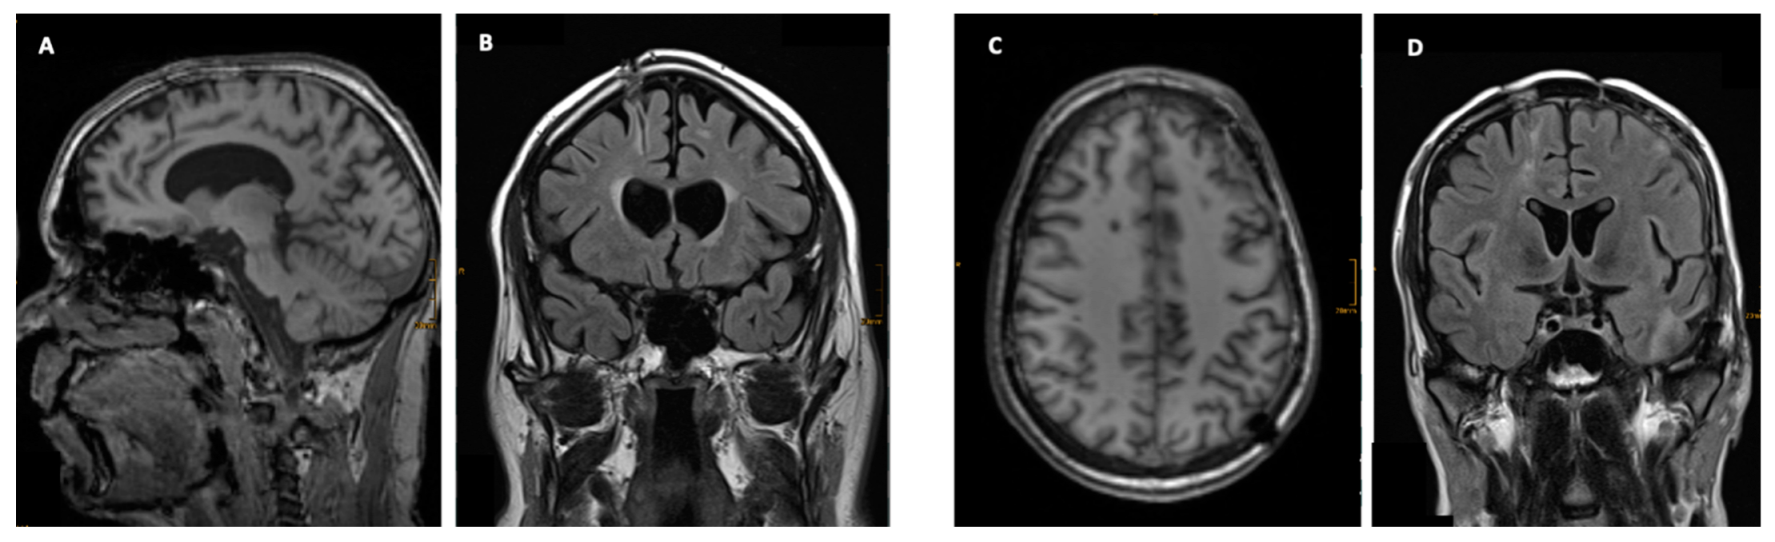

3.3. Imaging